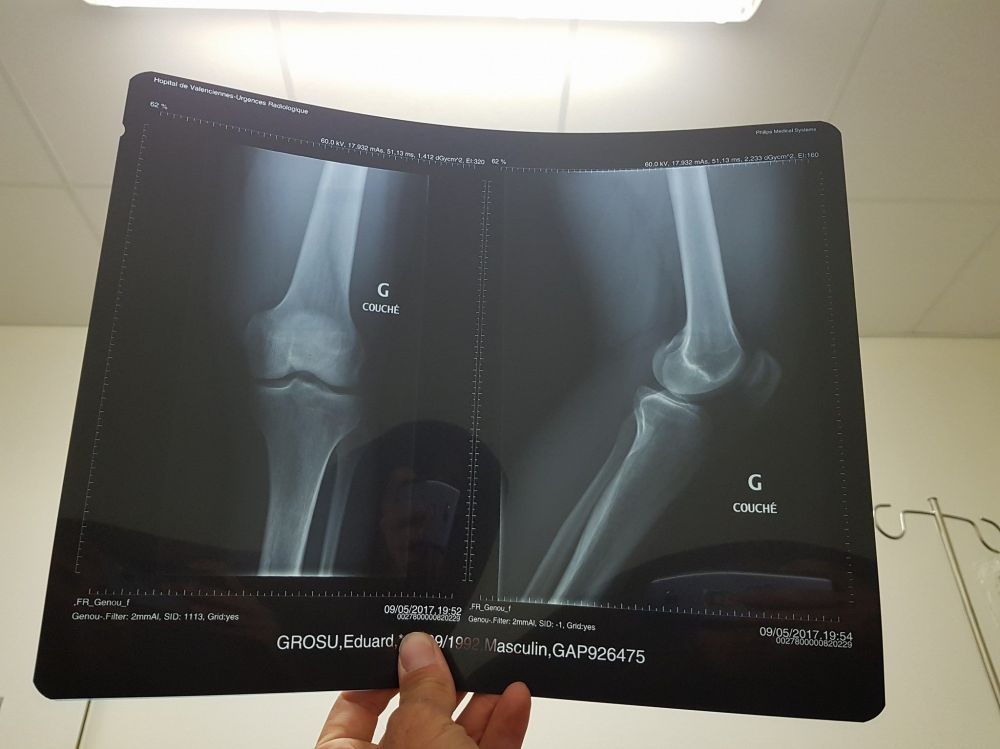

Eduard Grosu a căzut și s-a accidentat în prima etapă a întrecerii, marți, pe care a terminat-o – totuși, după care a ajuns de urgență la spital, unde a fost diagnosticat cu o fractură de rotulă (foto 2 – Facebook).